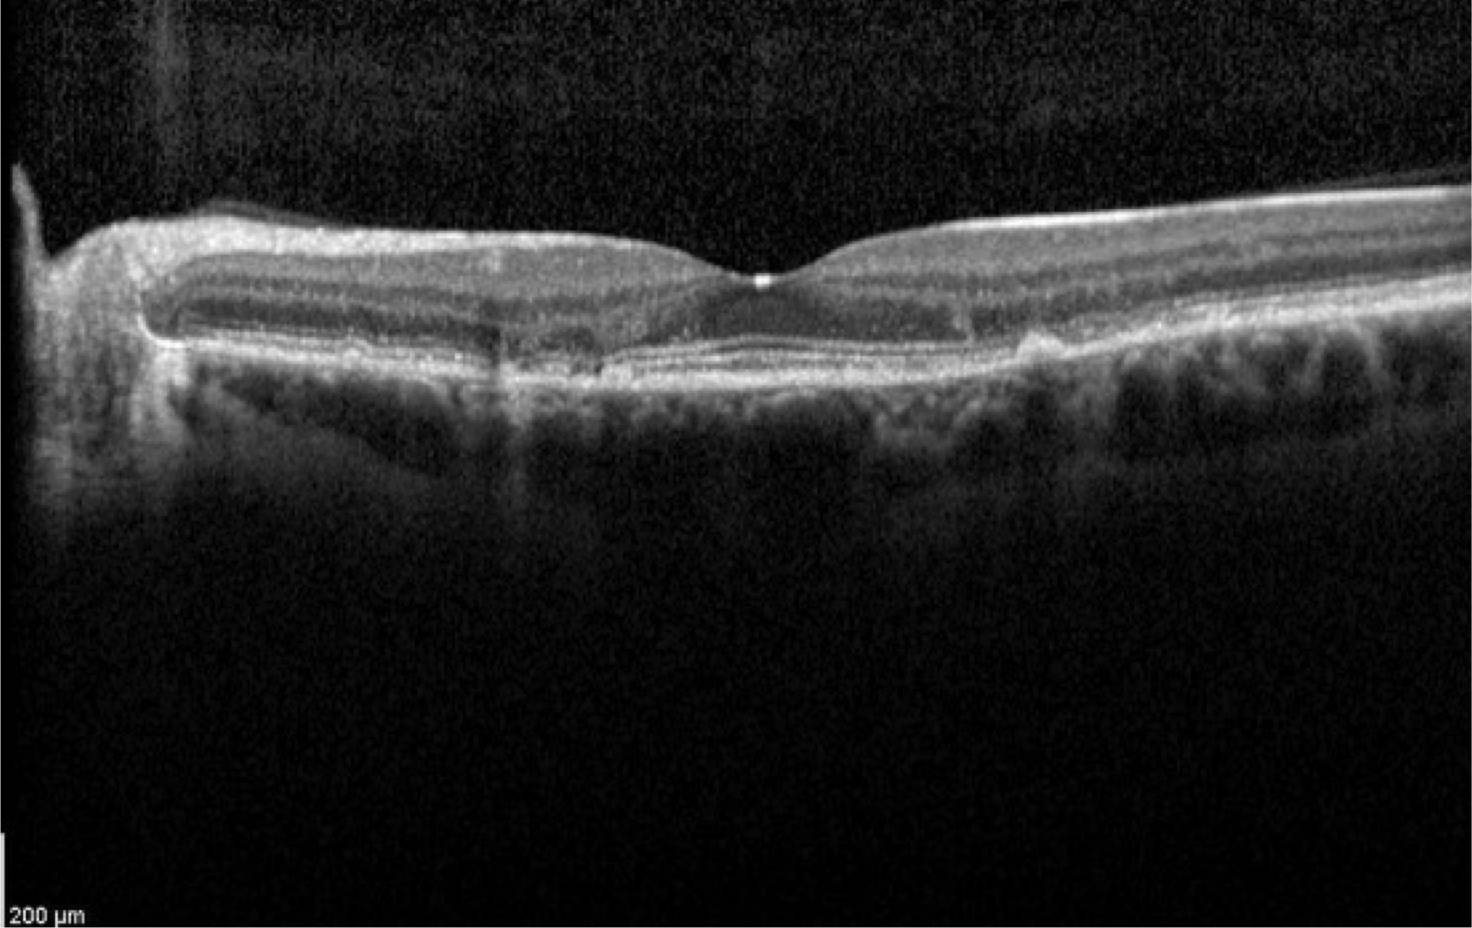

Case 8

Case 8 is a 38 year old woman with 20/20 vision. Both of her parents have good vision.

Optical coherence tomogram of the left eye.